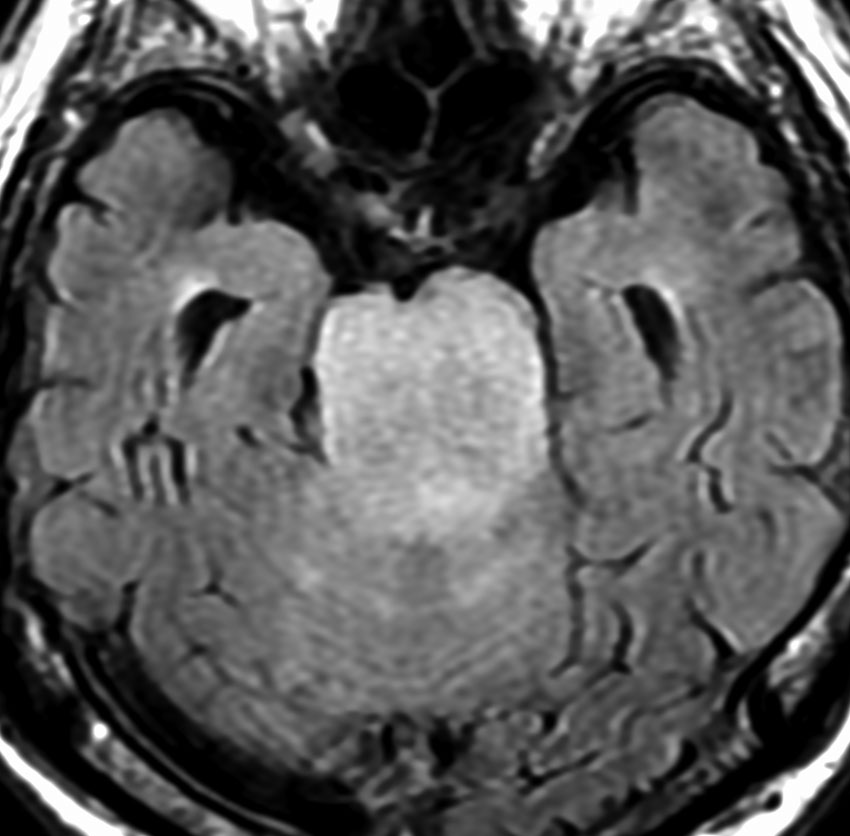

MRI画像所見 60代で嚥下障害と構音障害で発症した例

延髄から中脳まで腫瘍があって脳幹部が腫れています。この画像ですと,小児のびまん性橋膠腫(DIPG,びまん性正中グリオーマ)のように見えます

両側視床から大脳基底核,両側大脳半球深部白質,脳梁まで広範囲に腫瘍が存在します。退形成性星細胞腫のようにまだらにガドリニウム増強されます。